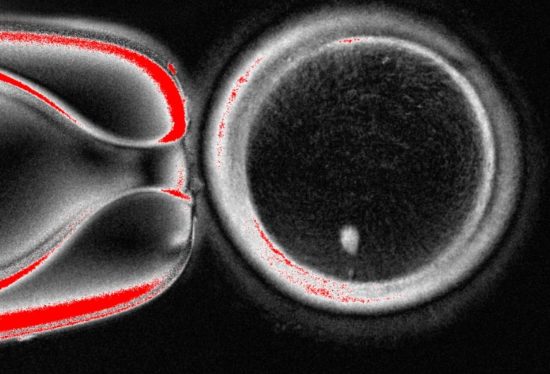

- El desafío:El proceso en humanos es complejo, ya que el ADN del óvulo normal y el núcleo del donante no pueden duplicarse al mismo tiempo.

- El avance:Para sortear este problema, los investigadores emplearon un método llamado «mitomeiosis», que fuerza al óvulo a dividirse y descartar un par de cromosomas, haciéndolo viable para la fertilización.

- Nuevo desarrollo:En el experimento más reciente, se crearon 82 óvulos funcionales, de los cuales un 9% se desarrolló hasta el estado de blastocisto